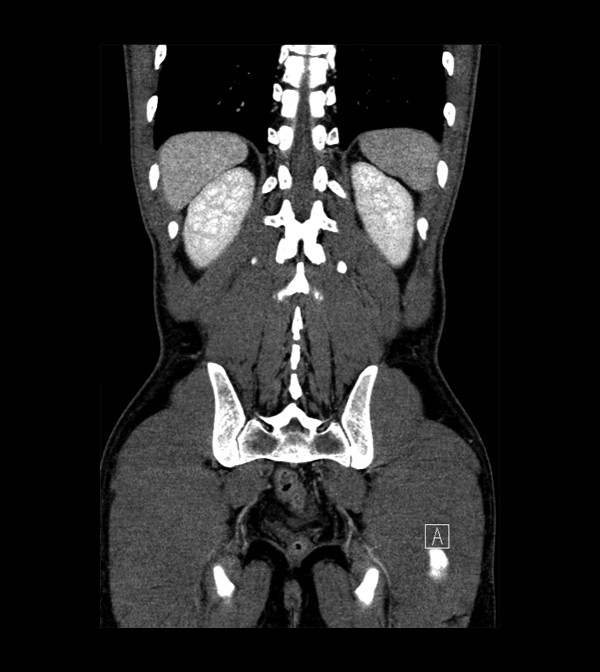

Body

Covers abdominal CT anatomy.